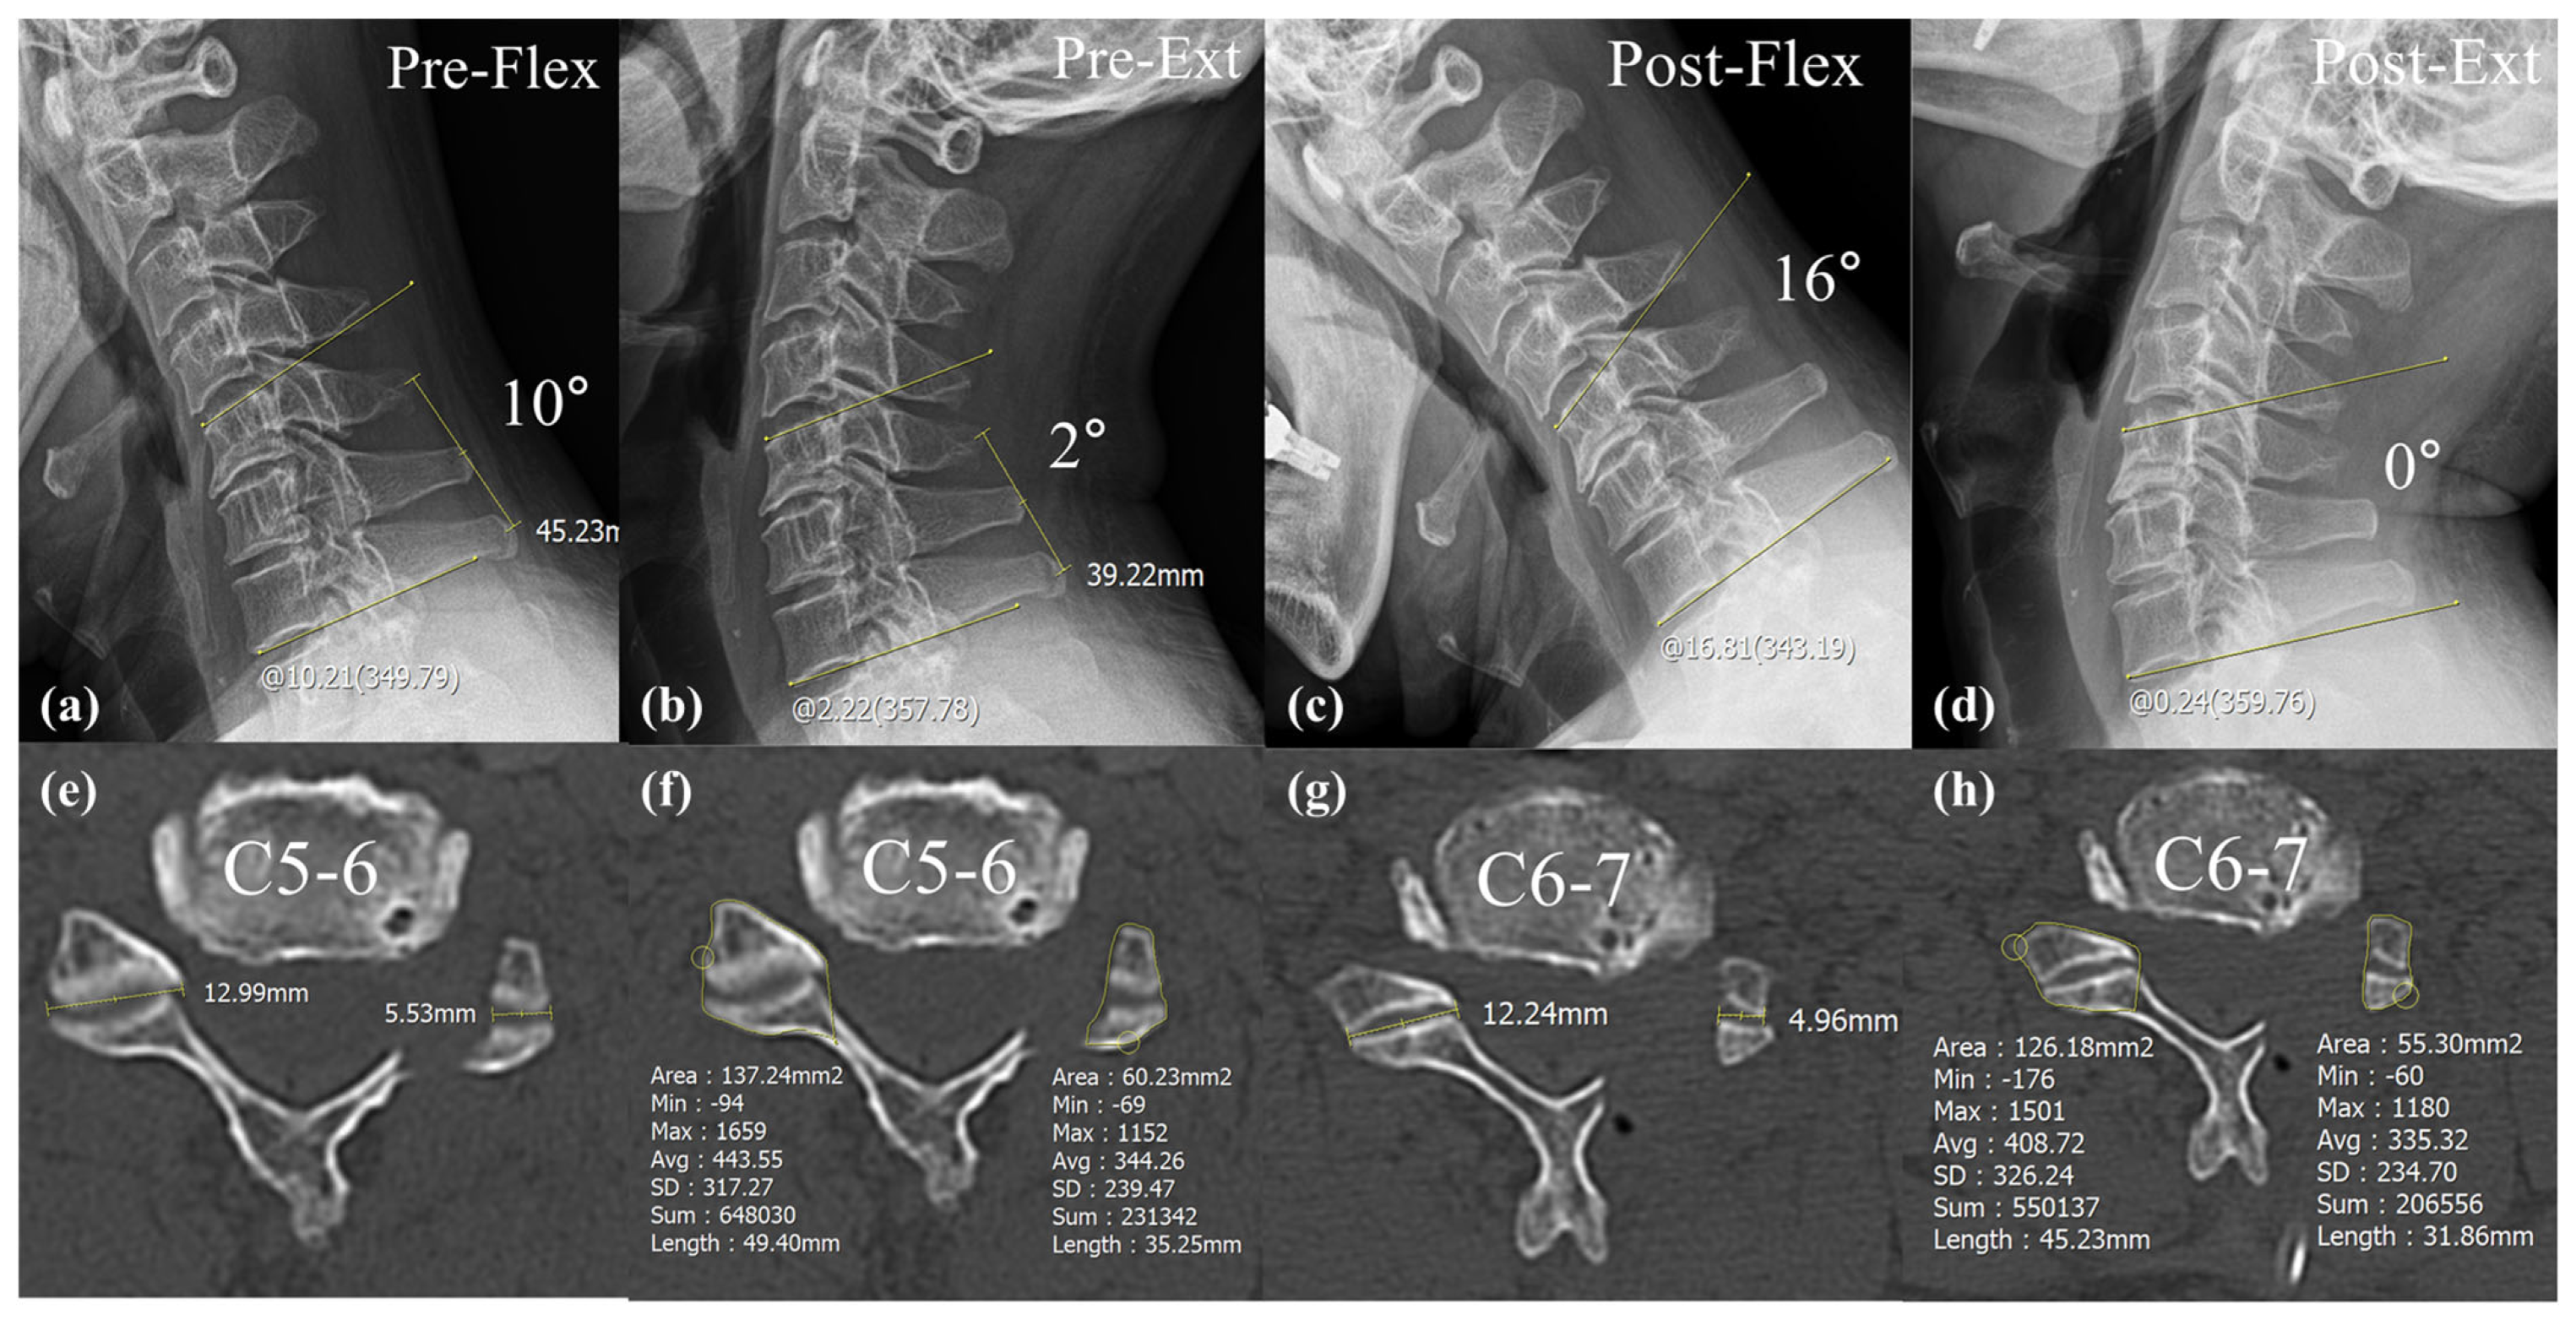

| ROM Segmental Angle | 17.1 ± 8.4 | 18.2 ± 10.2 | 0.52 |

| ROM Cervical Angle | 42.7 ± 17.5 | 42.4 ± 14.9 | 0.93 |

| Segmental Angle | −4.3 ± 6.5 | −0.5 ± 5.6 | 0.02 * |

| Cervical Angle | −11.8 ± 11.5 | −4.6 ± 8.0 | <0.01 * |

| ROM Segmental Angle | 5.2 ± 5.5 | 9.2 ± 6.3 | 0.01 * |

| ROM Cervical Angle | 18.0 ± 5.7 | 13.7 ± 6.4 | 0.21 |

| Segmental Angle | −3.8 ± 6.1 | −0.1 ± 4.6 | 0.01 * |

| Cervical Angle | −13.0 ± 12.3 | −4.7 ± 8.8 | <0.01 * |

| ROM Segmental Angle | 6.2 ± 5.6 | 15.2 ± 7.5 | <0.01 * |

| ROM Cervical Angle | 28.5 ± 6.7 | 22.8 ± 6.0 | 0.64 |

| Foraminal dimension (mm2) | 34.3 ± 8.5 | 31.5 ± 7.8 | 0.16 |

| Post foraminal dimension (mm2) | 54.5 ± 8.2 | 53.3 ± 7.4 | 0.51 |

| Foraminal enlargement (%) | 63.8 ± 26.1 | 75.5 ± 34.6 | 0.13 |

| Facetectomy width (%) | 43.2 ± 7.3 | 51.6 ± 11.3 | 0.01 * |

| Facetectomy area (%) | 40.5 ± 8.1 | 48.1 ± 10.4 | <0.01 * |